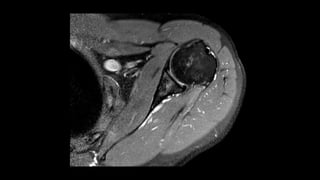

O documento aborda lesões no ombro, dividindo-as por faixas etárias: fraturas de clavícula em crianças, luxações em adultos e fraturas do úmero proximal em idosos. Descreve também técnicas de avaliação radiográfica e suas variações, incluindo incidências específicas para diagnóstico. Além disso, são mencionados métodos de imagem alternativos para a avaliação de partes moles e condições articulares.